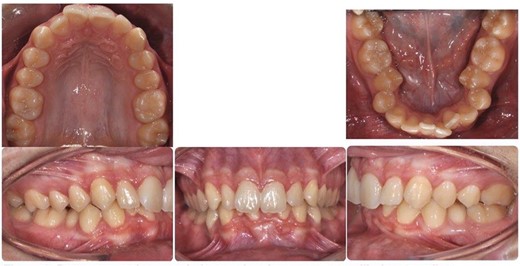

Post-treatment clinical examination showed that crowding was relieved by a 4-mm increase in the intermolar width of the maxillary and mandibular arches. In addition, a class I molar and canine relationship was achieved with good occlusion (Fig. 5) and a pleasing smile (Fig. 6). Post-treatment lateral cephalometric radiographs showed that the mandible had grown forward in the sagittal dimension, improving the skeletal profile (Fig. 7b). The upper incisors were proclined by 15° to achieve ideal labio-lingual inclination for optimum aesthetics; the lower incisor was optimally positioned to achieve ideal overjet and overbite (Fig. 7b). Mandibular anterior teeth were intruded to correct the impinging overbite and level the Curve of Spee. Finally, the patient was referred to an oral surgeon for extraction of the third molars.

Post-treatment intra-oral photos showing severe mandibular crowding